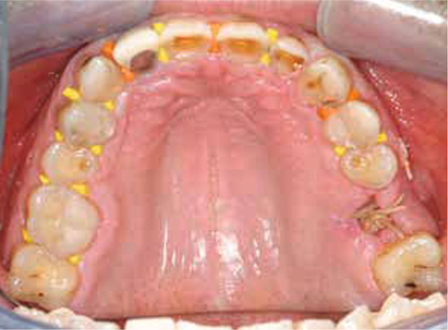

Bij het extraoraal onderzoek zie ik een lichte hypertrofie van de m. masseter. Intraoraal tref ik een ernstig versleten dentitie aan waarbij de slijtage niet passend bij de leeftijd kan worden genoemd (afbeelding 2-7 en tabel 1) .

Afb. 3

Occlusaal aanzicht van de bovenkaak.